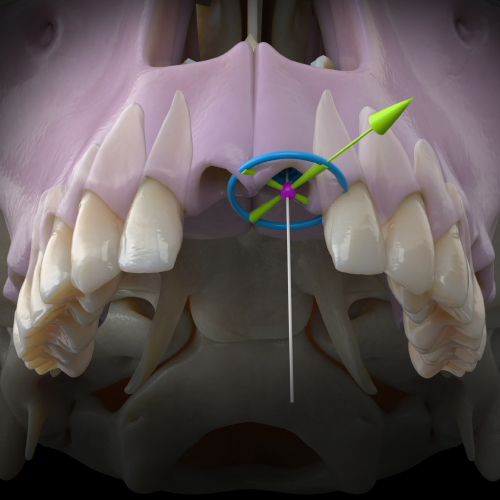

Dynamic Navigation for Dental Implants and Beyond—The Key to a Complete Digital Workflow

Robert W. Emery, BDS, DDS

Friday, March 29, 2024

This Compendium eBook offers a continuing education (CE) article that describes the various benefits and applications of dynamic navigation, and explains the workflows for implant surgery, including the workflow for full-arch reconstructions. Clinical examples are also provided in this arti...